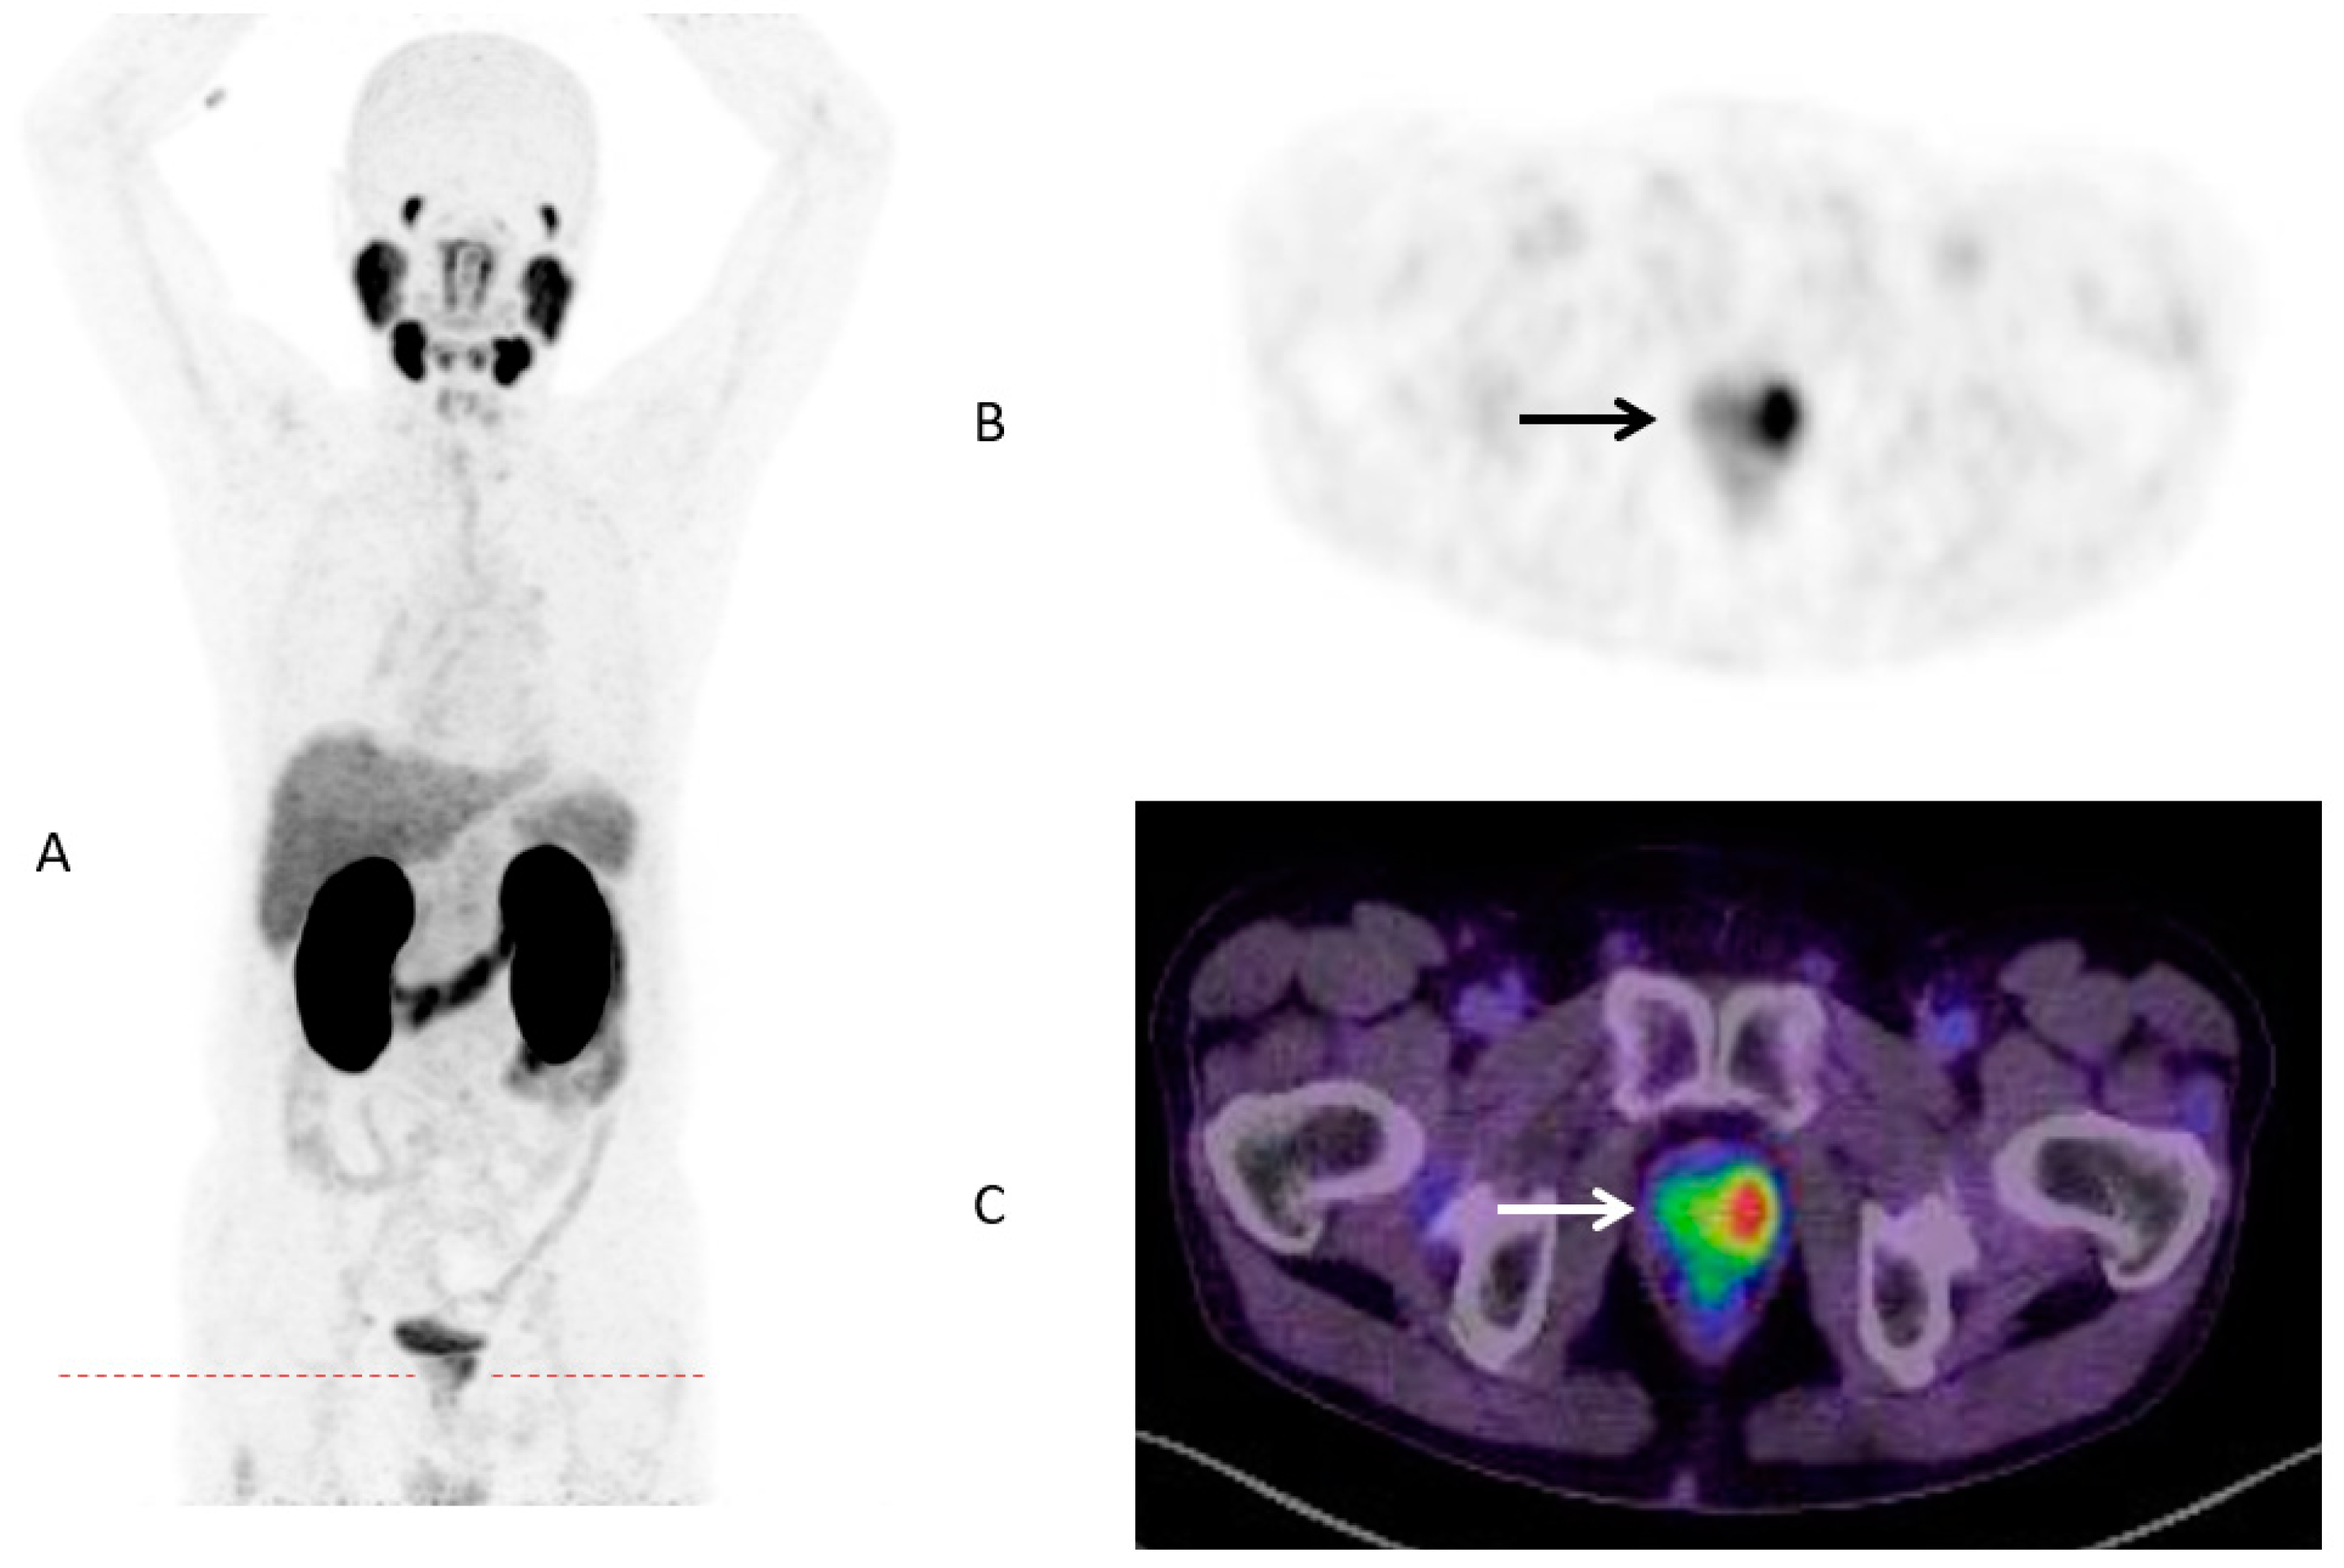

Until now, the identification of patient subgroups suitable for treatment escalation leading to improved survival is still challenging. Although numerous pretreatment risk stratification tools like the Memorial Sloan Kettering Cancer Center (MSKCC) nomogram or the Cancer of the Prostate Risk Assessment (CAPRA) score are available [27], there is a lack of evident data with regard to individual therapeutic consequences. Increasing numbers of PSMA-PET/CTs for primary staging around the globe confirms a great potential to that molecular imaging methodology. As published a few years ago, SUVmax of intraprostatic, malignant lesions was highly correlated with several clinical parameters like Gleason Score (GS) or PSA [28]. The present study observed a statistically significant higher SUVmax for men with metastatic disease (Figure 2 and Figure 3).

Figure 2.

PSMA-PET/CT in maximum intensity projection (MIP) (A) of a 70-years old patient with prostate cancer (GS 7b/group grade 3, PSA 4.53 ng/mL) and low intraprostatic SUVmax (3.45) and no metastases (B) PSMA-PET Dx; (C) PSMA PET/CT Dx.